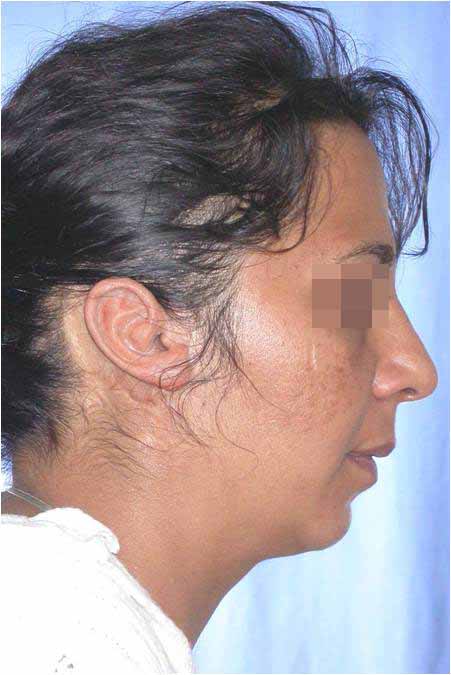

Лицева корекция преди и след лечението – случай на доц. Джоров